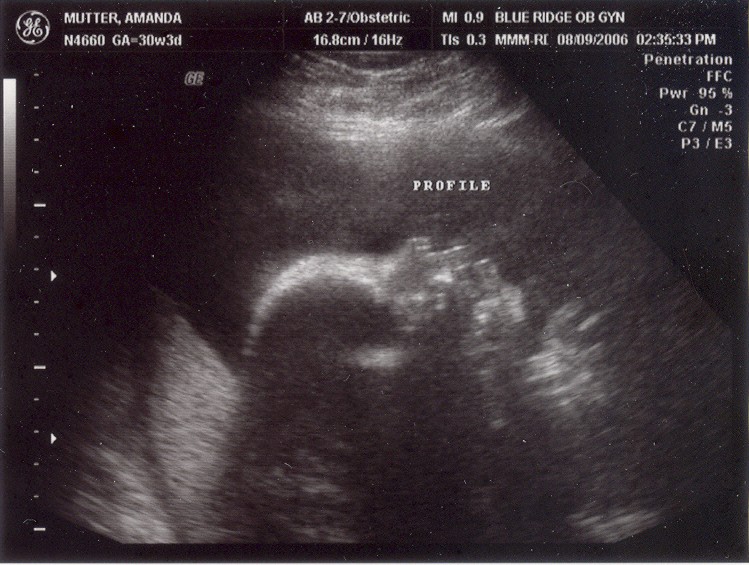

August 8, 2006: Another Ultrasound

Little did my parents know I'd be making my entrance in less than a month. The OB didn't suspect either :-)

My face is recognizable already.